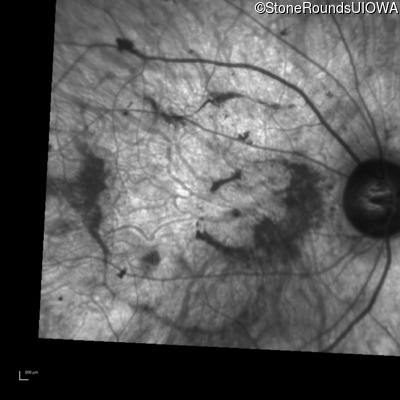

Infrared Fundus Photograph - Right - 20/200 +2

Exemplar